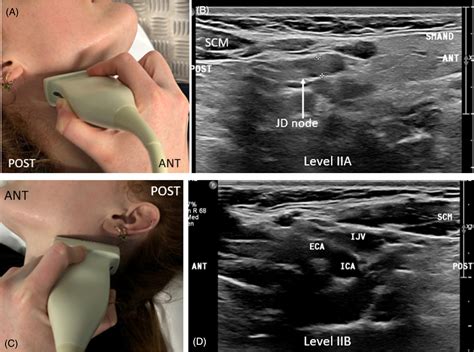

Lymph Node Sonography is a specialized form of ultrasound imaging focused specifically on evaluating the lymphatic system's nodes. Unlike other imaging modalities such as CT scans or MRIs, ultrasound is real-time, allowing the radiologist to observe blood flow patterns—a key indicator in distinguishing between reactive nodes (those fighting an infection) and pathological nodes (those potentially affected by cancer).

Undergoing Lymph Node Sonography is a straightforward process that typically takes about 15 to 30 minutes. You do not need to fast or prepare in any special way. During the procedure, you will lie on an examination table, and the sonographer will apply a clear, water-based gel to the area of interest. The transducer, a small handheld device, is moved across the skin to capture images from multiple angles.

The primary advantage of Lymph Node Sonography is its accessibility and safety. Because it does not use ionizing radiation, it is perfectly safe for children and pregnant patients. Furthermore, the ability to perform a "dynamic" exam means the doctor can ask you to swallow or turn your head while imaging to see how the node interacts with surrounding structures like blood vessels or nerves.